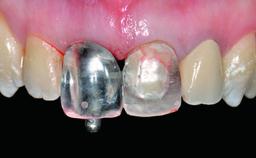

Replacement of a Failing Upper Left Central Incisor: Immediate Placement of an RC Bone Level Implant and Provisionalization

A healthy 23-year-old female patient was referred for a consultation on replacing tooth 21 with an implant-supported restoration. The patient had recently moved to the area and reported a history of endodontic and periodontal treatment for tooth 21. The tooth had been deemed non-restorable by her previous periodontist but since she was going to be moving, he recommended consulting to a dentist in her new city to continue her treatment. A review of her medical history yielded no significant findings and no known drug allergies. The analysis of her smile revealed a medium to high symmetrical smile line and a slightly discolored tooth 21.

Loading Protocol Immediate

Retention Cemented, with prosthesis margin < 3mm submucosal Cemented, with prosthesis margin < 3mm submucosal

Provisional Implant-Supported Prosthesis Prosthodontic margin < 3 mm apical to mucosal margin Prosthodontic margin < 3 mm apical to mucosal margin